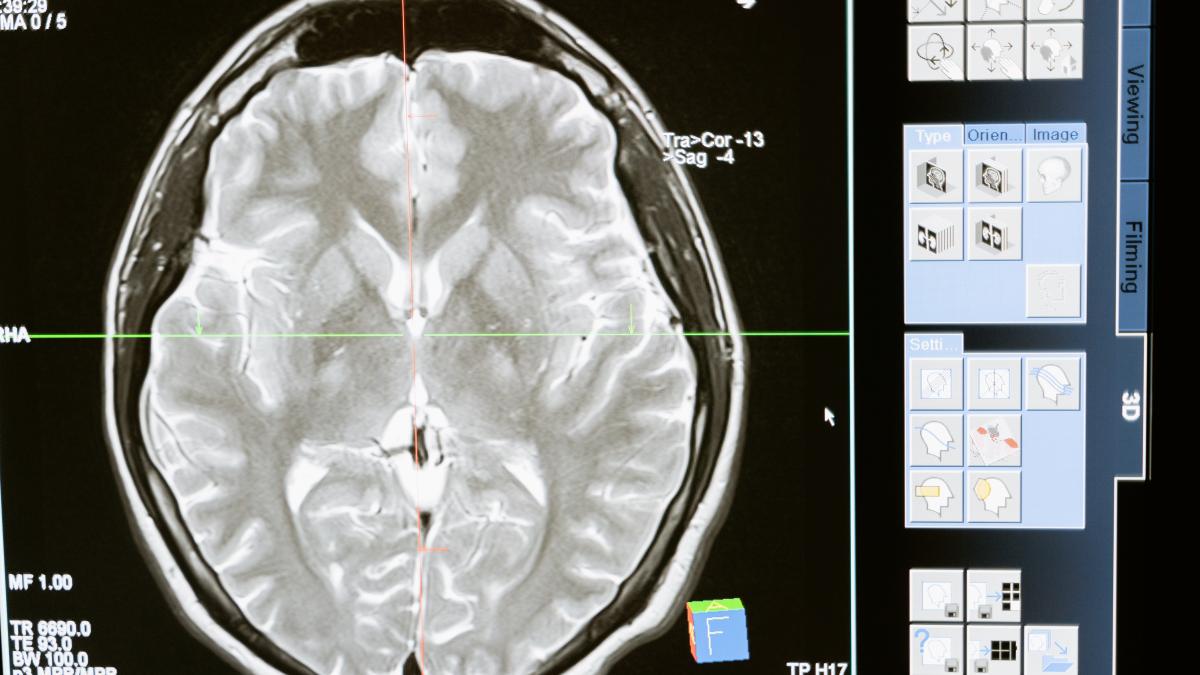

Medicii au găsit un vierme lung de 8 centimetri, viu, în creierul unei femei din Australia. Viermele a fost extras din țesutul deteriorat din lobul frontal al pacientulei, în timpul unei intervenții chirurgicale la Canberra în 2022.

Pacienta a fost internată la spital, unde un examen a evidențiat ulterior „o leziune atipică în lobul frontal drept al creierului” care necesita operație.